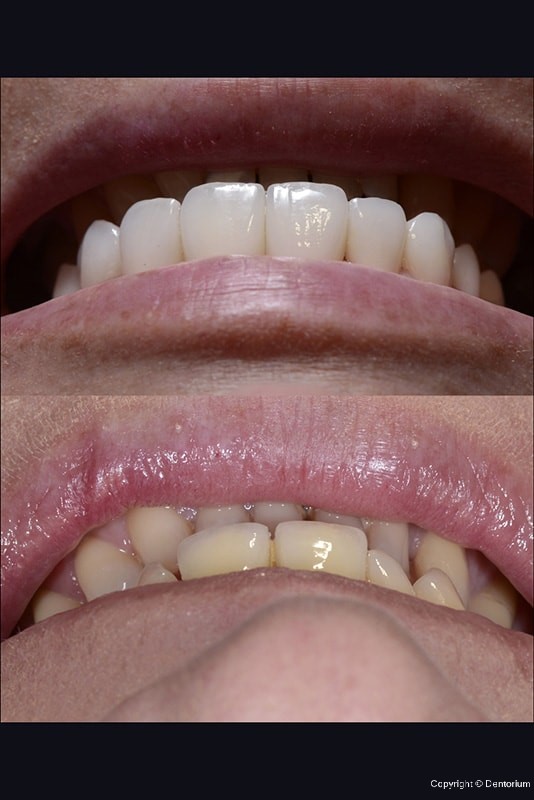

Complex functional - aesthetic rehabilitation

With the loss of teeth in aesthetic zone (front), the biggest challenge is soft tissue conservation. Due to limitation of tissue resource, precise and predictable treatment plan is of great importance. Also, in Suzana’s case we had to restore the function, and as a consequence achieved aesthetic of the smile, as well.